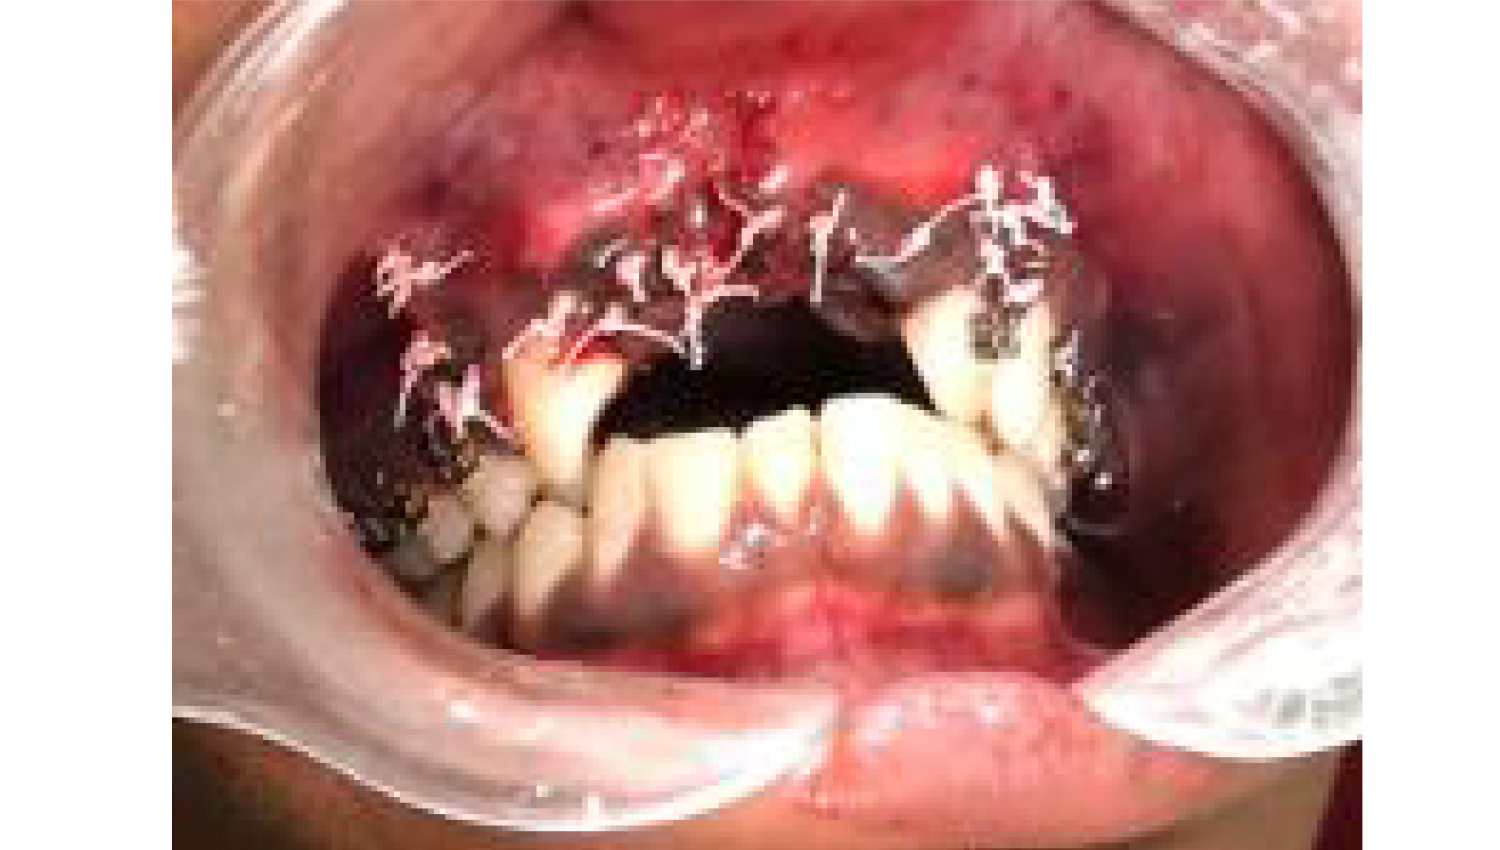

- Surgery was Complex Three Dimensional

- Augmentation with Khoury's Technique.

2.Complex Three Dimensional Augmentation procedure was applied to the patient with Khoury's Technique. Powerbone Gel and Cortical plate products were used during the process.

3.Final clinical view.